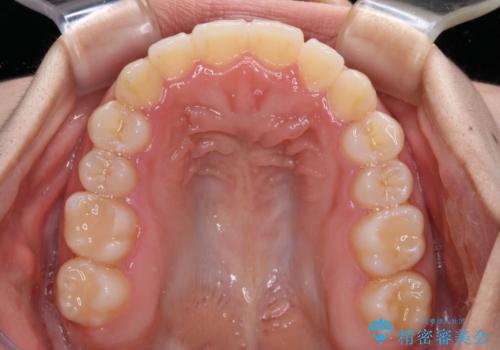

- 上下前歯のクロスバイトと叢生を気にして来院された患者様です。

インビザラインでの治療を希望されていて、デコボコの程度が中等度であり、安価なパッケージにて対応可能と判断されたため、インビザライン・モデレートを用いて矯正治療を行うこととしました。